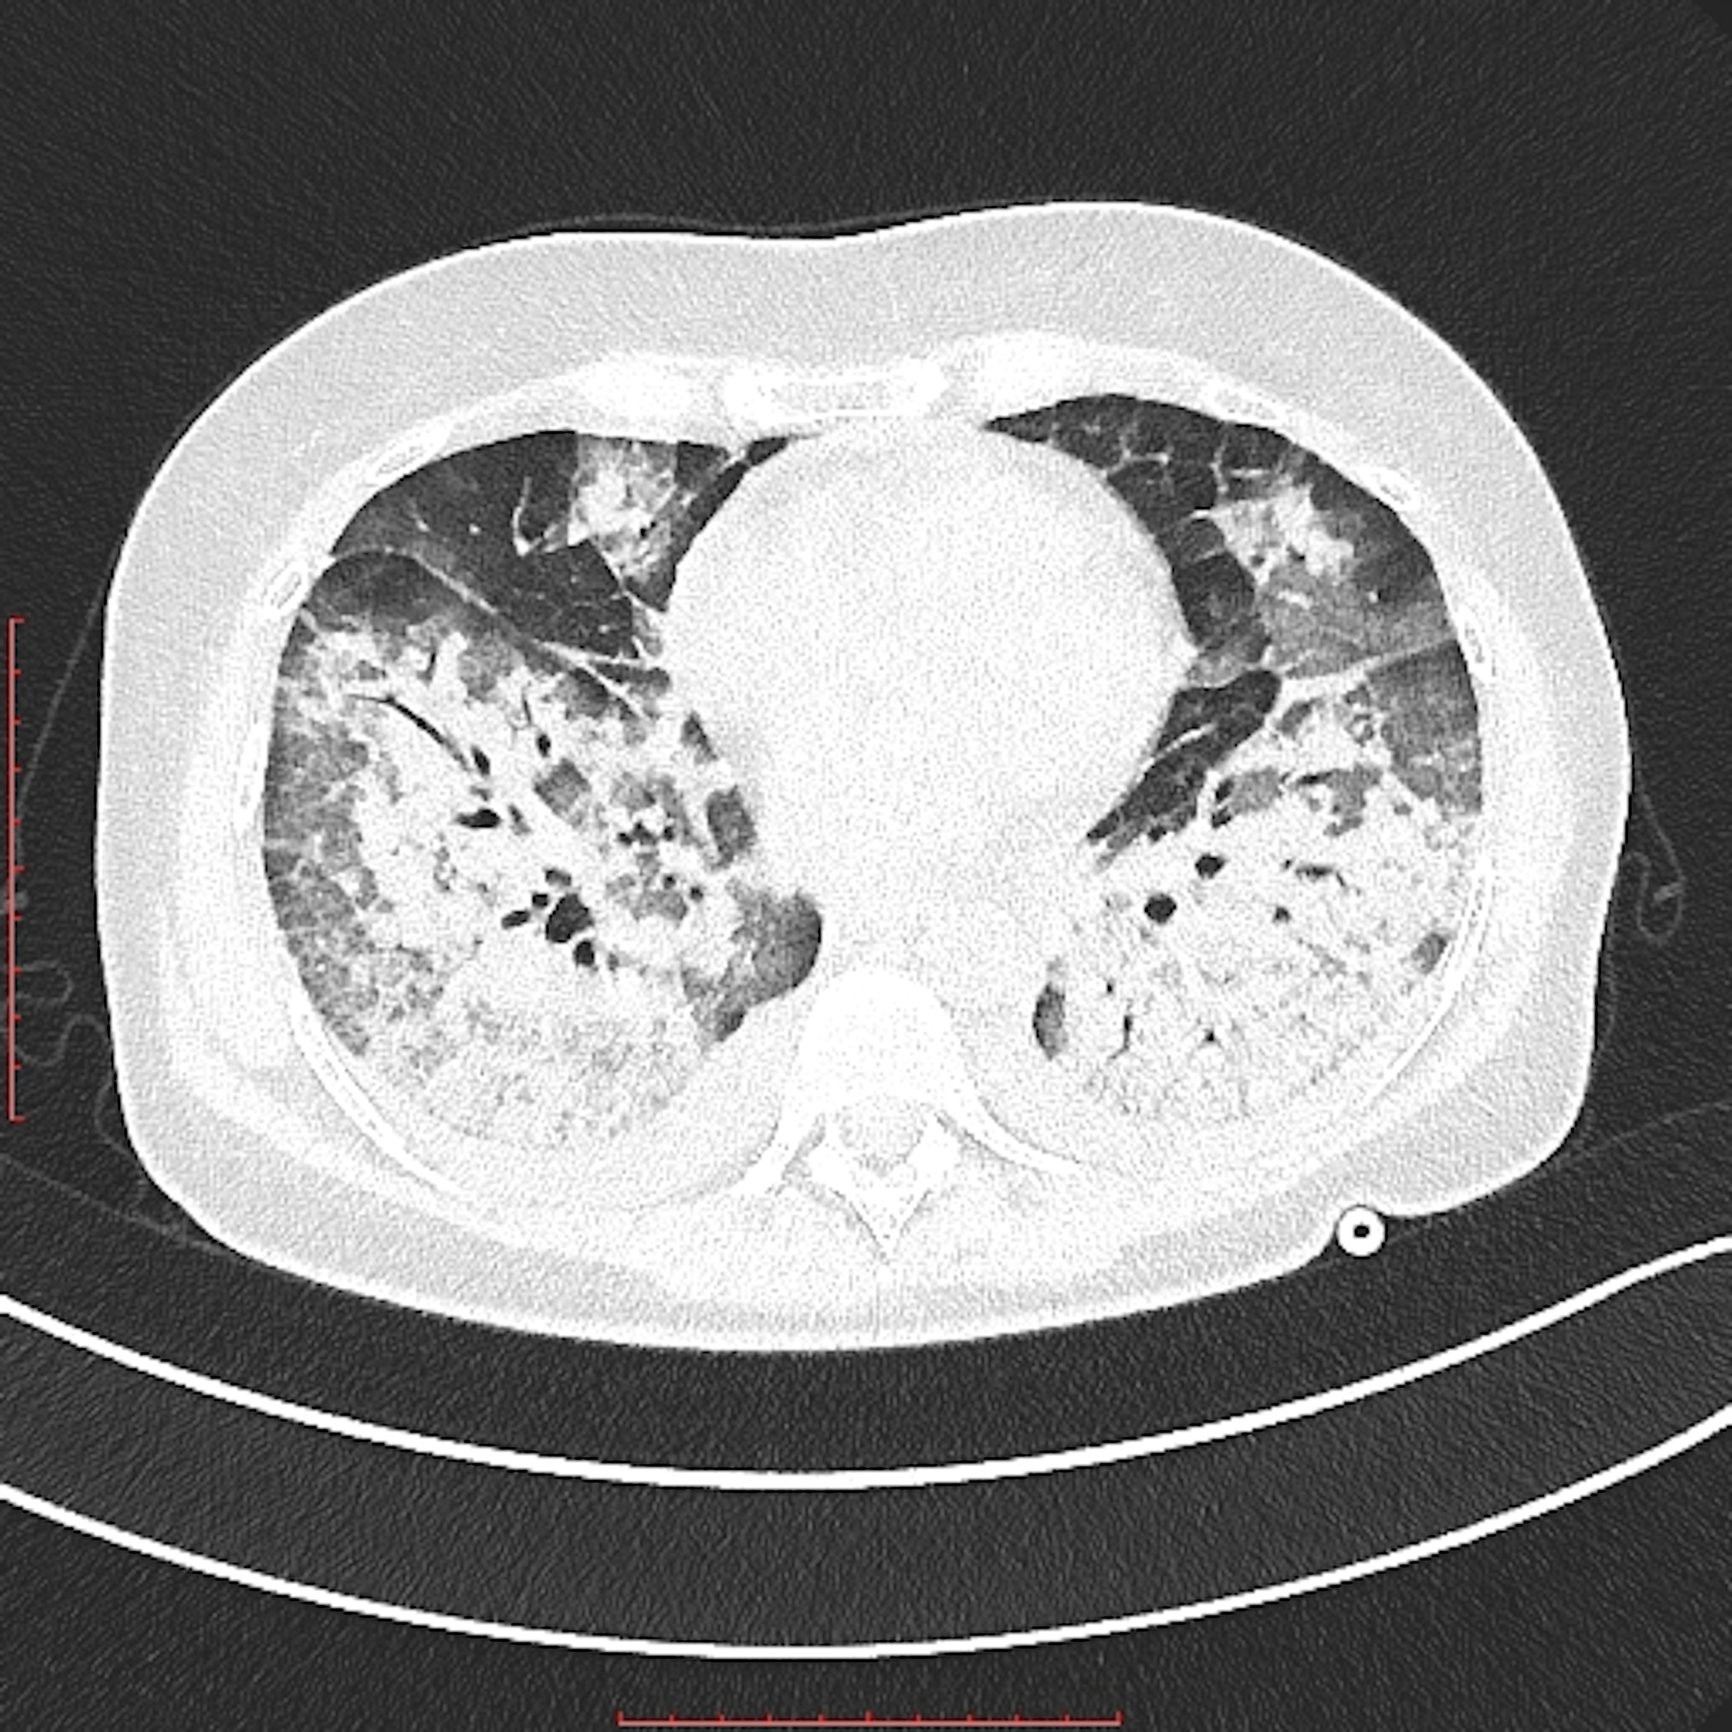

This photo gallery shows the variety of radiological presentations of COVID-19 (SARS-CoV-2) in medical imaging, including computed tomography (CT), radiograph X-rays, ultrasound, echocardiograms and magnetic resonance imaging (MRI). The radiology images show examples of typical COVID pneumonia in the lungs and the numerous complications the virus causes in the body in multiple organs, including the brain, kidneys, heart, abdomen and vascular system.

Ultrasound, especially hand-held ultrasound imaging devices, have become a primary imaging modality for novel coronavirus because of the ease to bag the device and sterilize it after use. CT and mobile X-ray systems are also used as front-line imaging systems for COVID-positive or suspected COVID patients.